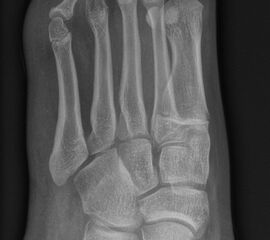

DMMO/DMDO (Distale Minimalinvasive Metatarsale Osteotomie/Distale Minimalinvasive Diaphysäre Osteotomie)

Die Indikation für eine DMMO oder DMDO (Distale Minimalinvasive Metatarsale Osteotomie/Distale Minimalinvasive Diaphysäre Osteotomie) beim Kind mit wachsendem Skelett ist nicht die klassische Metatarsalgie des Erwachsenen. In der Kinderorthopädie kann eine gute Indikation für die DMMO oder für eine DMDO der Ballen-Hohl-Fuß mit Metatarsalgie sein. Wird z. B. bei einer frühen Hohlfußkorrektur das Metatarsale I für eine bessere Rückfußeinstellung extendiert und zur Aufhebung der Extensorensubstitution die Sehne des M. tibialis posterior transferiert, kann sich im Verlauf eine Dysbalance der Metatarsalia entwickeln und eine Metatarsalgie unter II-IV auftreten. Mit einer DMDO werden die Köpfchen II-IV effektiv angehoben und die Beschwerden gebessert (Abb. 17 und 18).

Abb. 18 a-b: Beispiel einer DMDO beim Hohlfuß d.p. (dorso-plantare) Ansicht (a) und schräge Ansicht (b).

Zum Lesen der Bildbeschreibung und zur Vollansicht bitte die Bilder anklicken. Bilder: A. Helmers.